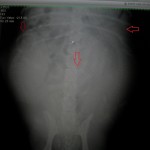

出産1週間前にレントゲンを実施し、胎子が何頭いるか、骨盤から出て自然出産できそうかを見ていきます。胎子の頭の大きさが大きすぎたら帝王切開を考えて、計画出産する必要があります。